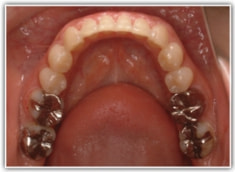

反対咬合ケース

治療法:表の矯正(T21ブラケット)

治療前